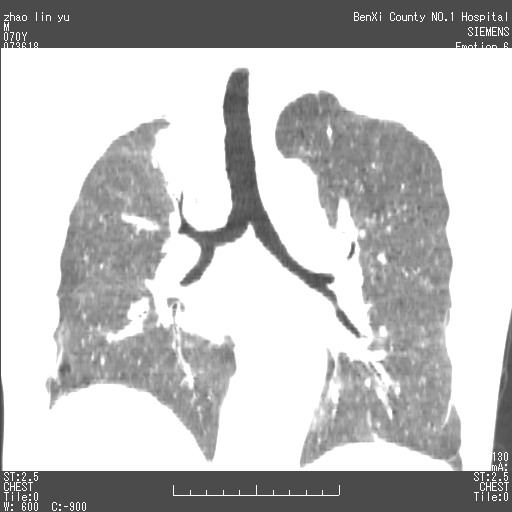

以下是引用王靖旗在2007-7-10 17:12:00的发言:[br] 男、70、咳嗽两个月,半年前换瓣手术,胸片未见异常,于昨天行x片发现右肺上野大片影,行ct扫描,这里是减薄图像,余肺正常。明天晚上会有增强扫描片,到时我会上传。[br][br] 冠状位请大家细看,应该是有意义的,[br][br] 请大家先看平扫发表意见。[br][br]

[br]冠状面[br]

以下是引用zhangzhongshou在2007-7-10 21:43:00的发言:[br]右肺上叶周围型肺癌,以孤立型细支气管肺泡癌可能性大。